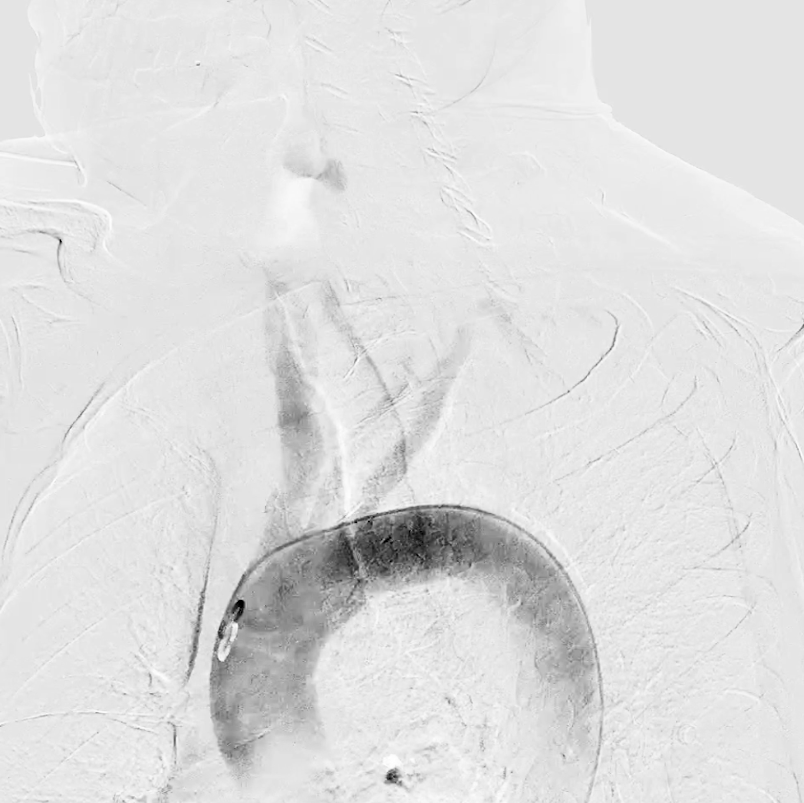

主动脉弓造影确认分型为Ⅰ型弓,为后续操作提供解剖参考

★ 病变评估

左侧颈总动脉造影:明确左侧颈内动脉闭塞,侧支循环通过颈外动脉部分供应颅内血流;

右侧颈总动脉造影(正位、汤氏位、侧位):明确右侧颈内动脉重度狭窄,病变远端直径5mm、近端直径8mm,长度约30mm,远端锚定区条件理想。